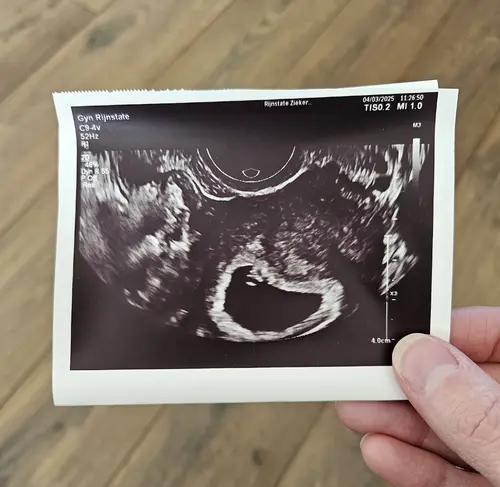

Daar is 'ie dan. Eigen berekening 7.5 weken, wordt nu geschat op 7.3 - 7.5 dus dat komt mooi overeen. Ik had in eerste instantie een uitwendige echo, maar er zat een waas over het beeld, dus we hebben daarna een inwendige gedaan. Heel blij met het beeld wat we toen zagen: een kloppend hartje ❤️.